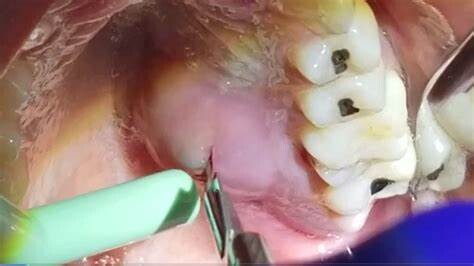

Treating a Tooth Abscess

You will almost certainly need antibiotics, and the abscess or pocket of pus on the gums might need to be lanced so it can be drained. When we can catch a tooth abscess soon enough, root canal treatment could save it. Unfortunately, if the infection is severe, the only solution may be to remove the tooth to help the infection drain adequately. Leaving the tooth in place could cause additional oral health problems, especially as the infection will have killed the tooth nerve, and there will be no blood flow to the tooth root to help fight the infection.